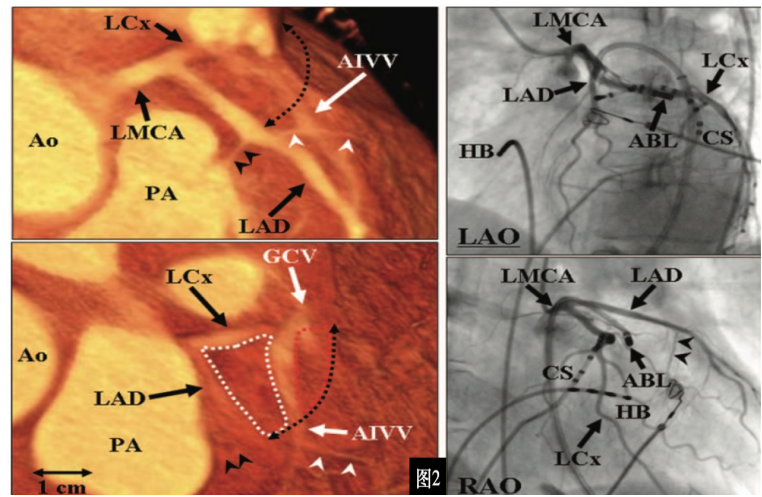

病历显示,该患者左室summit区(LVS)包括心外膜部和心内膜部(图2):心外膜部为左冠状动脉回旋支(LCx)、前降支(LAD)和心大静脉(GCV)形成的心外膜三角形区域,因心大静脉和前室间静脉(AIV)都位于此处,又可称为GCV/AIV区。GCV将心外膜LVS分为上部和下部,上部邻近冠状动脉且覆盖心外膜脂肪组织,故也称为消融不可到达区域,而下部则为心外膜导管消融可能到达区域。该区域位于左室出口部外侧,距冠状动脉较近,且部分位置表面覆盖厚脂肪层,此处室早的消融不仅风险大而且消融导管难以到达,故一直被电生理界认为是室早消融的难点。起源于该区域的室早一直是心律失常最具挑战性的起源部位之一,消融成功率低,治疗难度大。然而,干性心包穿刺外膜消融技术的出现,为解决这一难题提供了新的希望。